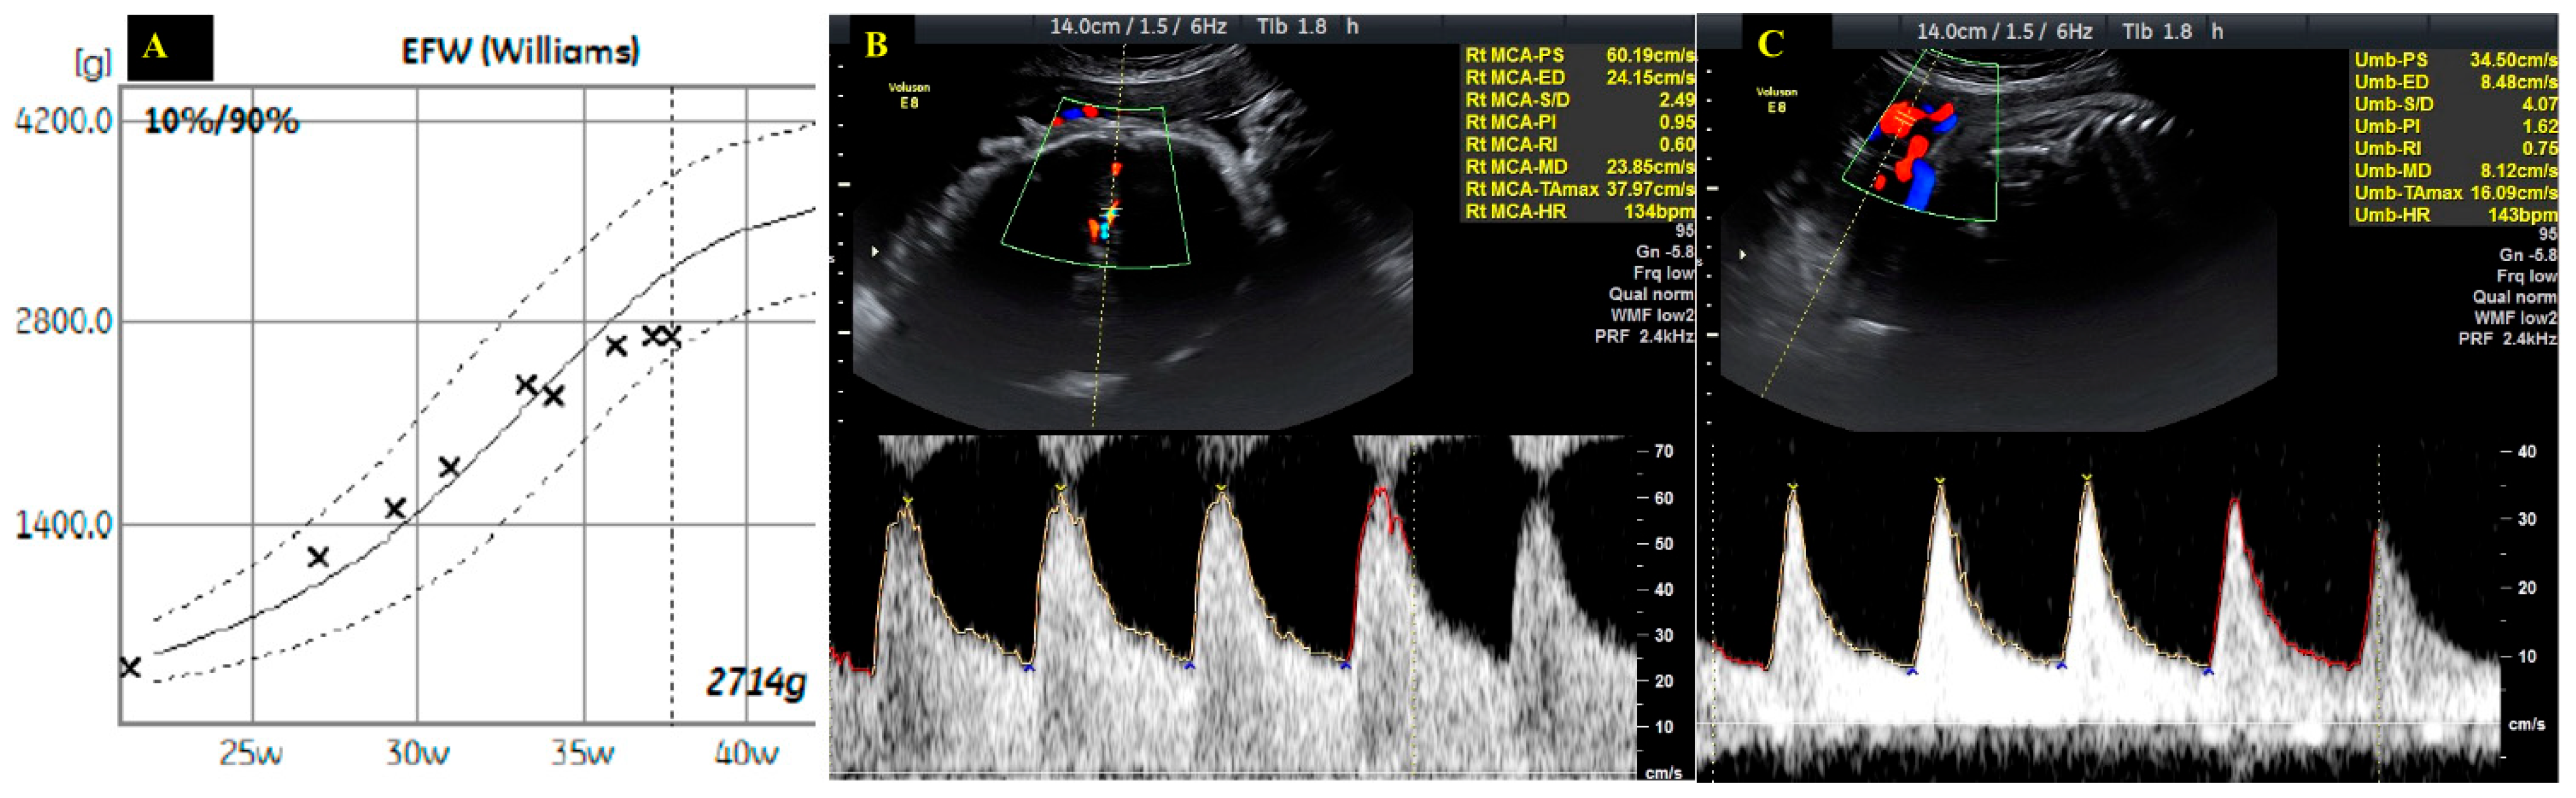

| Gestational Age (Weeks) | Heart Rate (bpm) | Hb (g/dL) | NT-proBNP (pg/mL) | 6mWT (m) | LVEF (%) | LVOT VTI (cm) | AV VTI (cm) | Maximum AV Gradient (mmHg) | Mean AV Gradient (mmHg) | Indexed Aortic Valve Area (cm2/m2) |

|---|---|---|---|---|---|---|---|---|---|---|

| 22 | 76 | 11.5 | 45 | 670 | 59 | 27.5 | 99.3 | 96 | 58 | 0.475 |

| 26 | 73 | 60 | 27.3 | 99.2 | 94 | 60 | 0.475 | |||

| 29 | 82 | 11.4 | 59 | 625 | 60 | 26.9 | 99.8 | 93 | 60 | 0.463 |

| 30 | 85 | 61 | 27 | 102 | 108 | 60 | 0.457 | |||

| 31 | 81 | 60 | 26.9 | 101.8 | 95 | 58 | 0.469 | |||

| 32 | 78 | 12.1 | 67 | 630 | 59 | 27.2 | 100 | 103 | 62 | 0.469 |

| 33 | 76 | 59 | 27.5 | 99.5 | 100 | 61 | 0.475 | |||

| 34 | 84 | 61 | 27.9 | 101 | 101 | 60 | 0.475 | |||

| 35 | 82 | 12.5 | 37 | 615 | 61 | 28 | 100.6 | 95 | 55 | 0.481 |

| 36 | 80 | 60 | 26.4 | 99 | 89 | 52 | 0.463 | |||

| 37 | 85 | 12.6 | 62 | 27 | 100 | 93 | 56 | 0.469 | ||

| 38 | 86 | 12.3 | 66 | 575 | 62 | 26.5 | 99.8 | 92 | 55 | 0.457 |

| 3 months postpartum | 70 | 11.9 | 54 | 654 | 60 | 28.3 | 118 | 103 | 68 | 0.50 |